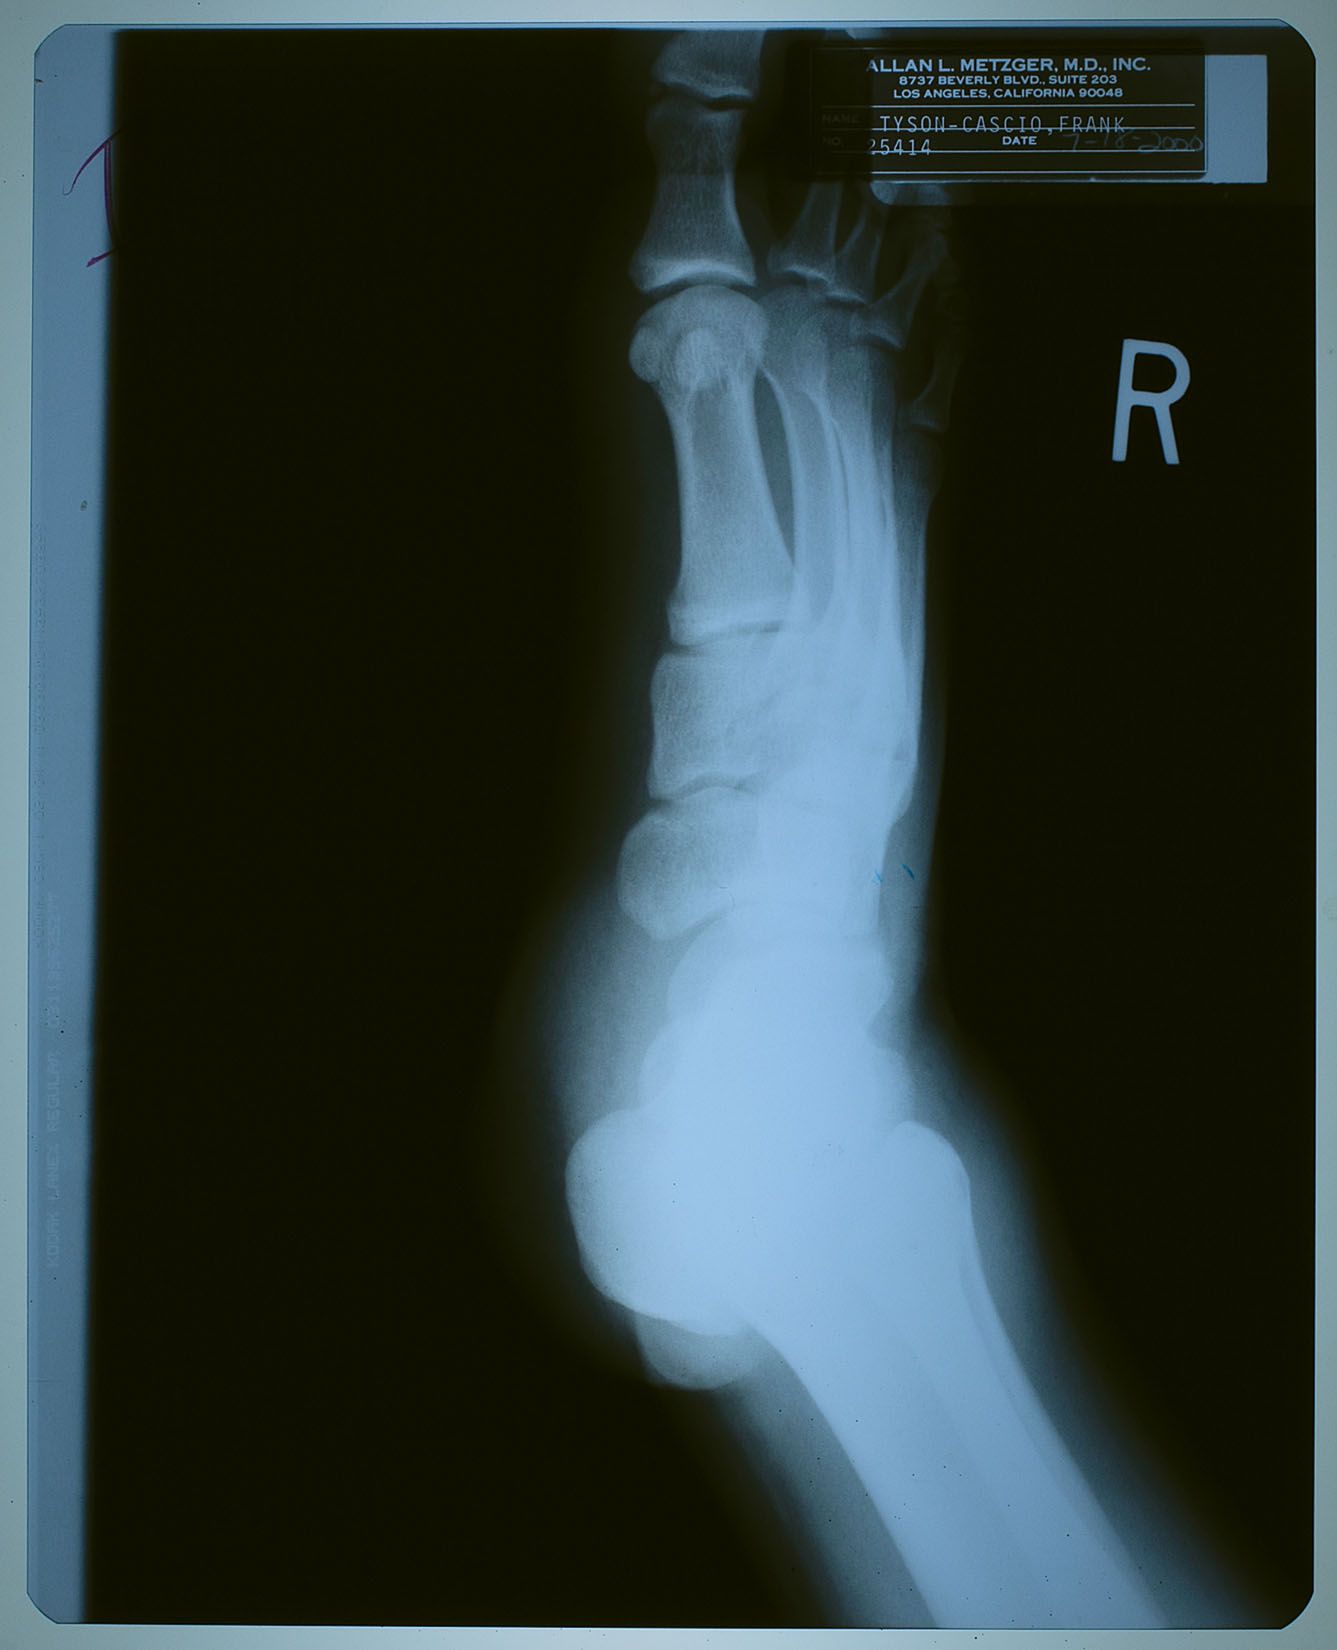

2000年7月18日、ネバーランドで子供たちと遊んでいて

怪我をした時に撮ったX線写真。

名前が 「タイソン-カシオ,フランク」 になっているけども、

カシオ本を読んだ御仁はお判りでしょう。

"タイソン" というのは、前年からマイケルの代理人を務めるようになった

フランク・カシオ君の仕事上での通名。

診療所などでは、マイケルがプライバシー面からフランク君の名を使う事もあったそう。

松葉杖を持っていないし、大事には至らなかった様子。

ただし、よく見ると靴はサンダルっぽいので、捻挫ぐらいにはなっちゃったかも?